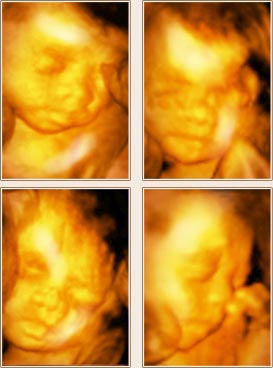

四四维彩超宝宝照片

- 出生前100天

- 出生后100天

- 在检查的同时,美国GE-E8四维彩超利用四维成像技术(4D),直观、立体地显示人体器官的三维结构及动态、实时地观察立体结构,高清显示腹中宝宝的实时动态“动画”,记录宝宝的一举一动,并可刻录成高清视频光盘留念。这不仅是独一无二的孕期纪念,也是送给未来宝宝的珍贵礼物。